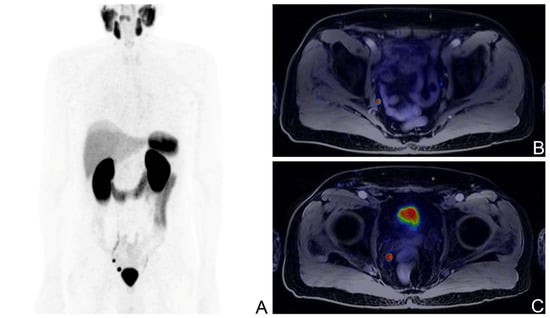

[68Ga]Ga-PSMA-11 PET was positive in 39/80 patients (median PSA: 0.43 ng/mL, range: 0.13–4.66) and negative in 41/80 (median PSA: 0.3 ng/mL, range: 0.01–5.22). On a regional basis, [68Ga]Ga-PSMA-11 uptake was observed in correspondence of the prostatic fossa in 6/39 patients (15%), of lymph nodes in 27/39 patients (69%), of bone in 12/39 patients (31%), and in the lungs in 1/39 patients. Among the 27 patients with lymph-nodal [68Ga]Ga-PSMA-11 uptake, 20/27 showed involvement of regional lymph nodes only, 4/27 solely non-regional lymph nodes, and in 3/27 [68Ga]Ga-PSMA-11 uptake was present in both regional and non-regional lymph nodes. Five patients with PSA < 0.2 ng/mL showed pathological findings at PET, all of them presenting pT ≥ 3a (Figure 1 and Figure 2).

Figure 1. [68Ga]Ga-PSMA-11 PET/MR scan of a BCR patient with the ISUP score of 3, pT3b after RP; PSA levels at the time of the scan: 0.14 ng/mL; Maximum Intensity Projection image (A), fused axial PET/MR views showing a pathological right iliac lymph node (B), and a pathological right pararectal lymph node (C).